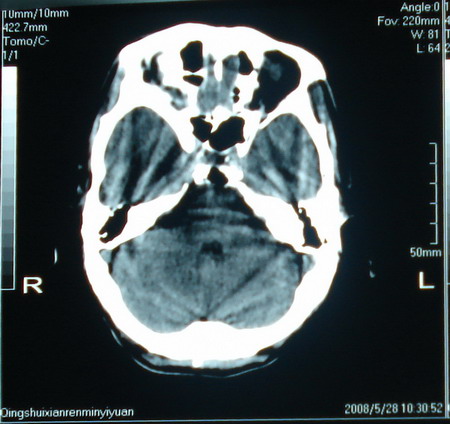

标题: CT13794:M63Y,头颅CT平扫 [打印本页]

标题: CT13794:M63Y,头颅CT平扫

男,63岁,头痛,呕吐,意识模糊一周。无发烧及感染史。

胶质瘤

胶质瘤可能性大。

胶质母细胞瘤

小肿瘤大水肿,考虑转移瘤

支持右侧丘脑恶性胶质母细胞瘤可能性大,建议增强进一步检查。